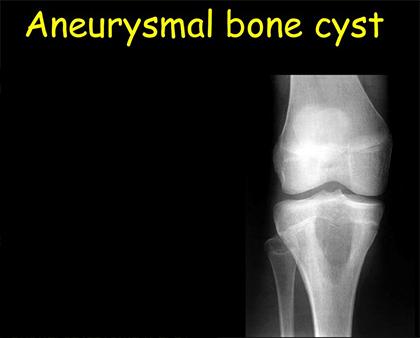

ANEURYSMAL BONE CYST

We have often heard of cyst formation in many parts of the body and such rare benign tumor formation in the bone is termed as aneurysmal bone cyst. This condition can occur in any bone but is common in bones like spine, pelvic bone and patellar region. In this condition, a blood filled lesion occurs, which may grow in size. Though the tumor is benign it can still be very fatal and causes a lot of discomfort in the affected person.